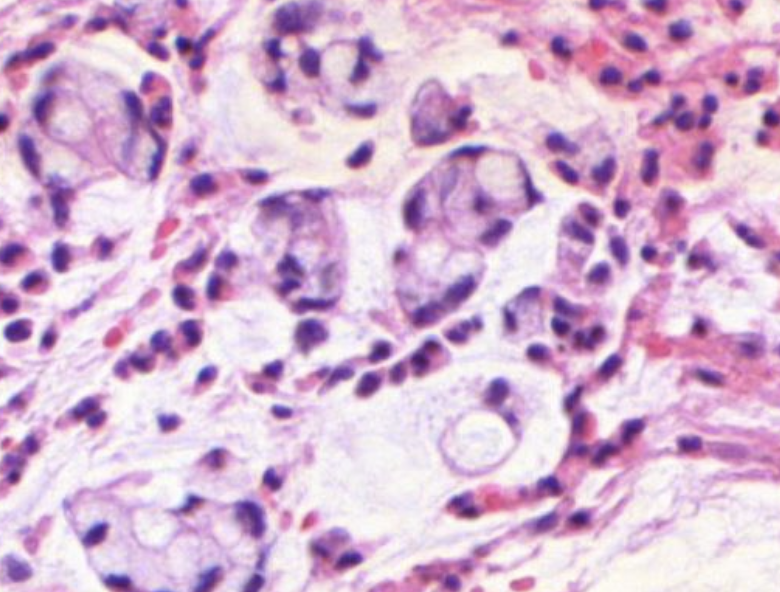

24) (Folie 24) Was zeigt das Bild eines invasiven Plattenepithelkarzinoms?

Histologisches Beispiel eines invasiv wachsenden Plattenepithelkarzinoms mit irregulären Tumorzellnestern in stromalem Gewebe.

36) (Folie 36) Was wird an der hochvergrößerten Darstellung demonstriert?

Kernatypien und Mitosen in höherer Vergrößerung zur sicheren Erkennung der Kriterien (z. B. pleomorphe Kerne, auffällige Mitosen) für die Gradbestimmung.